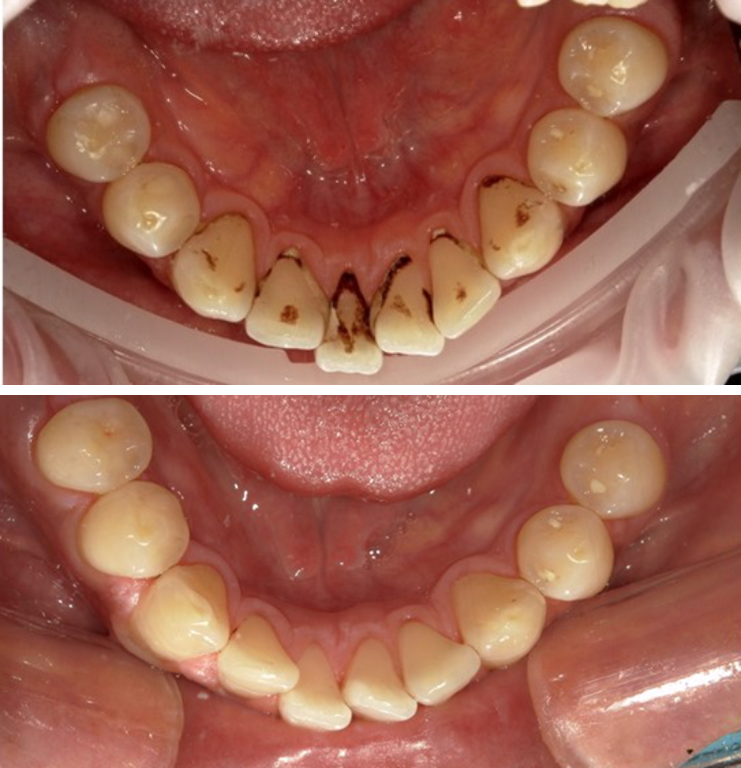

写真上:スケーリング前、写真下:スケーリング後